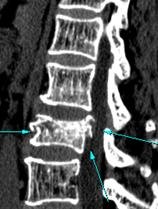

척추압박골절은 척추에서만 볼수있는 골절형태로

방사선검사나 자기공명영상 검사상[MRI]

척추의 본래 형태인 직사각형이 아닌

척추압박골절의 전형적 특징인

쇄기모양[사다리꼴]의 척추압박골절 형태를 나타내게 됩니다.